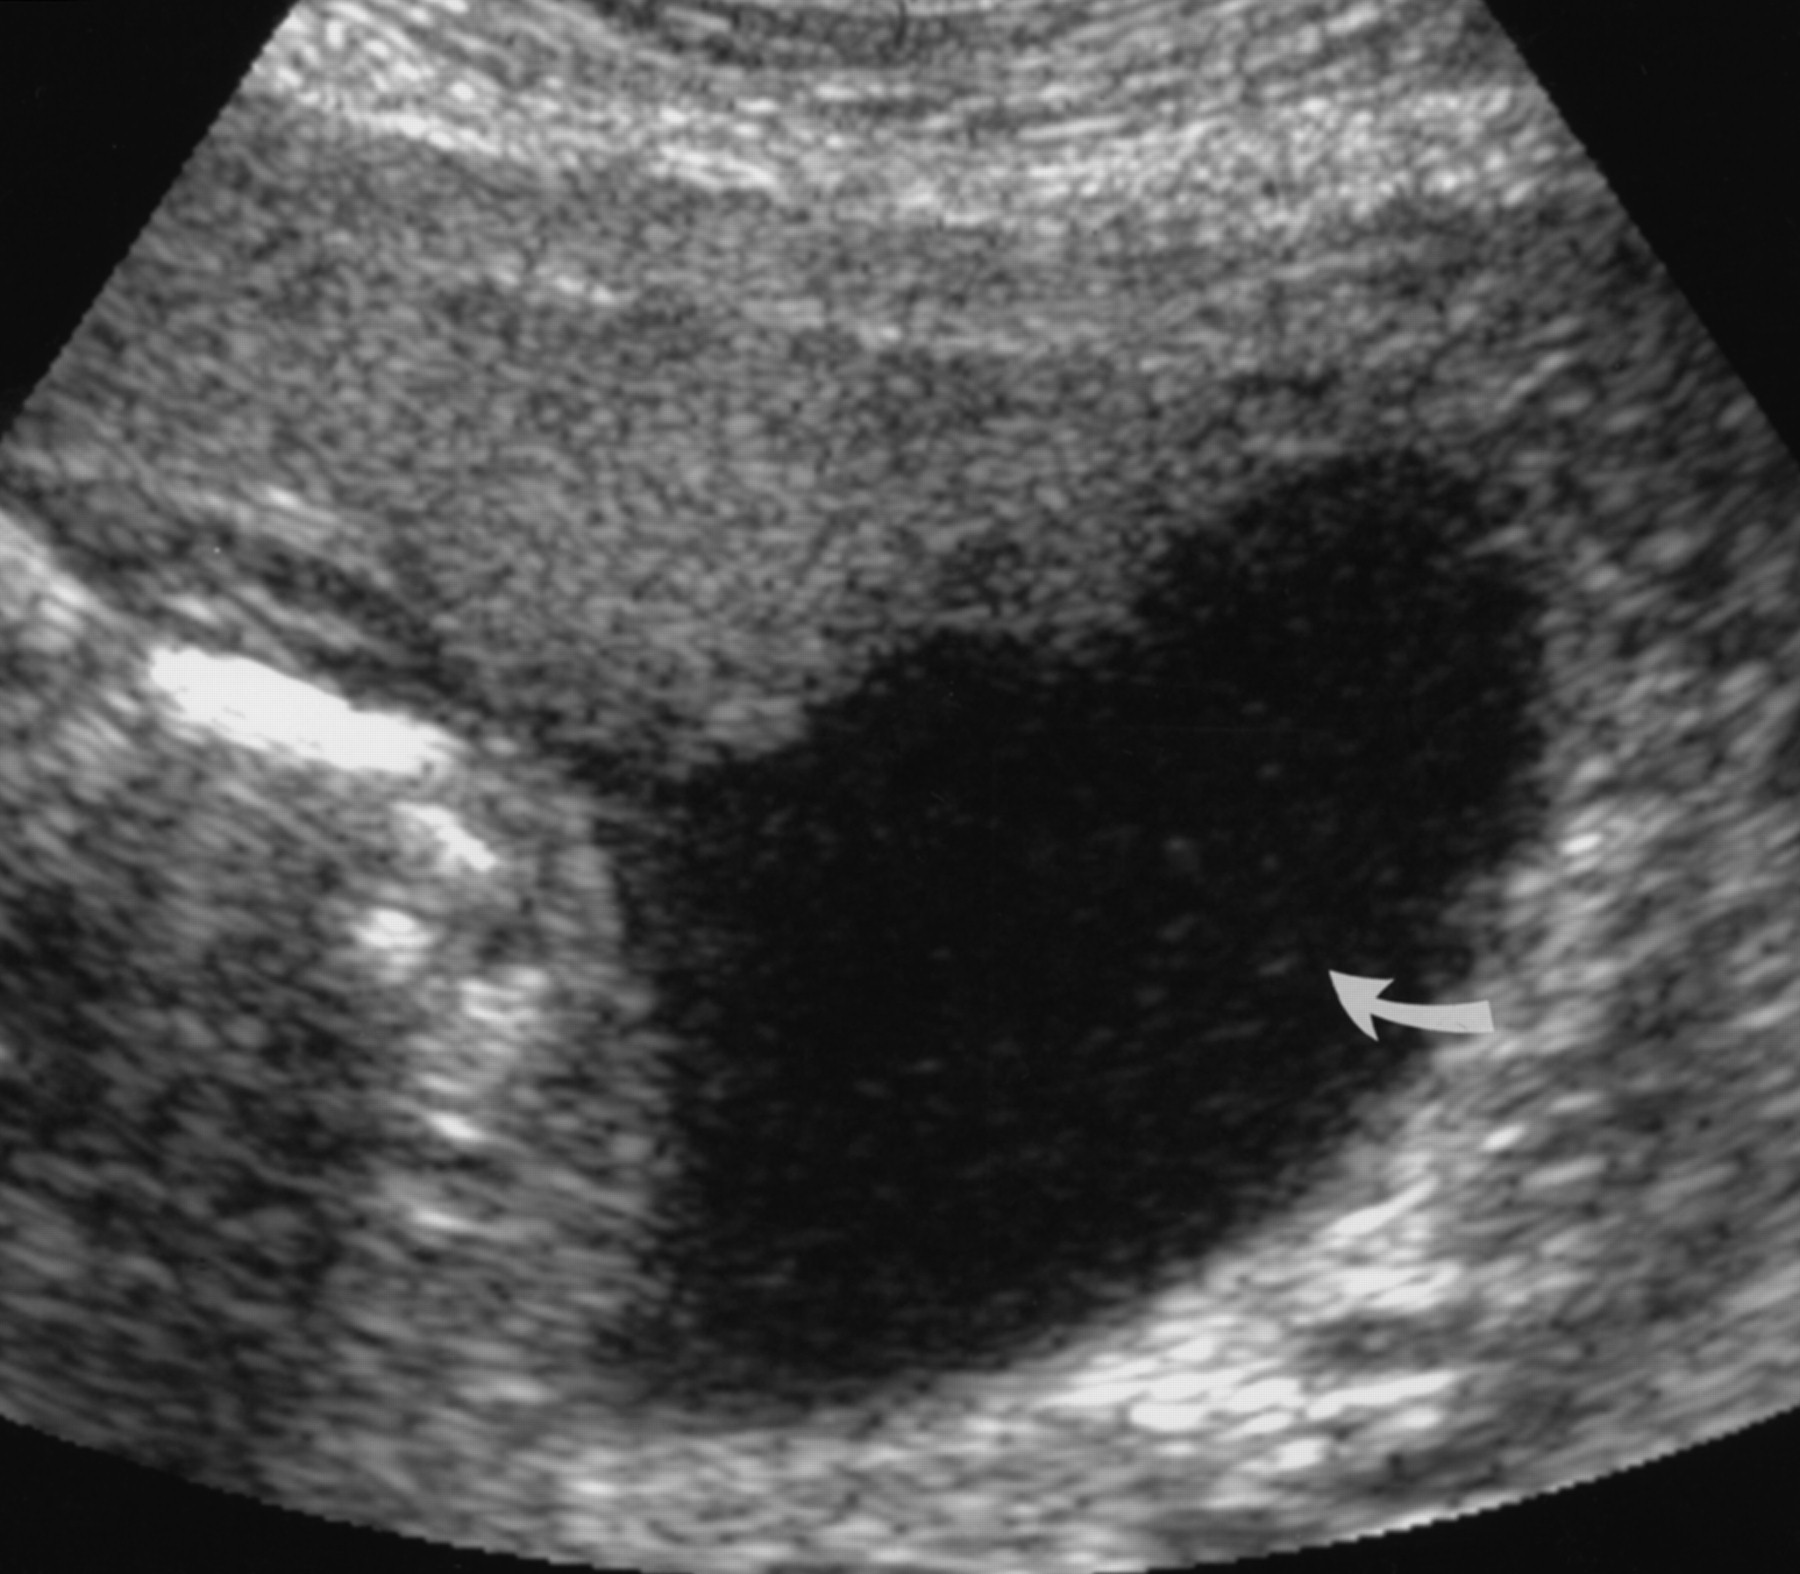

양수 인덱스 5cm 이하 (또는 가장 양수가 많은 곳의 깊이가 1 cm 이하)를 양수 과소증이라고 하는 데 양수 인덱스 수치 2 cm 이하인 경우는 심한 양수 과소증으로 부르는데 이때는 진통 중 태아 심박 저하 현상이 흔히 동반되기도 합니다.